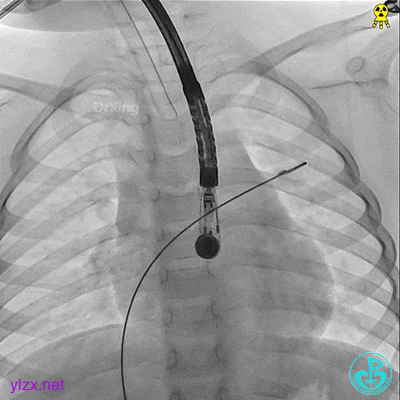

左盘展开

左盘展开,牵拉成型线,使左盘面成型。